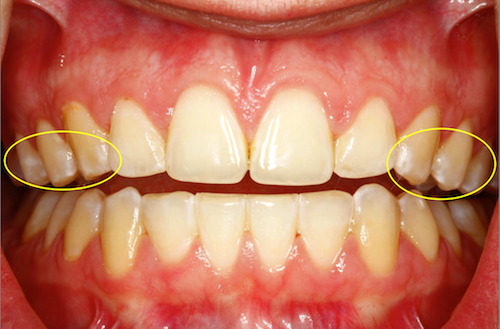

Most studies report the incidence of new clinically visible WSL occurring during orthodontic treatment to range between 30 to 70 percent of patients. Upper anterior teeth, especially maxillary laterals, are most commonly affected.